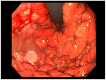

Gastric and esophageal tumors are diverse neoplasms that involve mucosal and submucosal tissue layers and include squamous cell carcinomas, adenocarcinomas, spindle cell neoplasms, neuroendocrine tumors, marginal B cell lymphomas, along with less common tumors. The worldwide burden of esophageal and gastric malignancies is significant, with esophageal and gastric cancer representing the ninth and fifth most common cancers, respectively. The approach to diagnosis and staging of these lesions is multimodal and includes a combination of gastrointestinal endoscopy, endoscopic ultrasound, and cross-sectional imaging. Likewise, therapy is multidisciplinary and combines therapeutic endoscopy, surgery, radiotherapy, and systemic chemotherapeutic tools. Future directions for diagnosis of esophageal and gastric malignancies are evolving rapidly and will involve advances in endoscopic and endosonographic techniques including tethered capsules, optical coherence tomography, along with targeted cytologic and serological analyses.